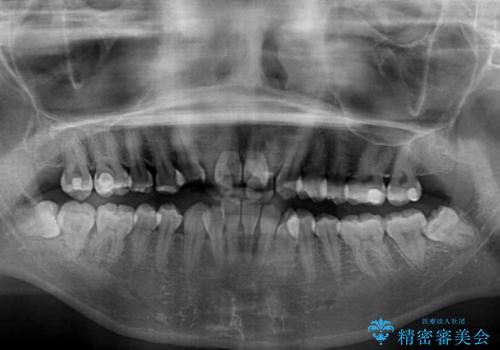

- 前歯の著しい叢生とクロスバイトを気にして来院された患者様です。

叢生が強いため、一見すると抜歯矯正と判断したくなりますが、下顎臼歯が舌側に倒れていることから、上顎骨を側方拡大し、非抜歯矯正の可能性を検討することとしました。

非抜歯矯正が可能となった場合には、インビザラインにて矯正治療を行うこととしました。

急速拡大装置による上顎骨の側方拡大が思った以上にうまくいき、非抜歯での矯正が可能となりました。

内側に倒れていた下顎の臼歯は起き上がり、清掃性も大幅に改善されました。